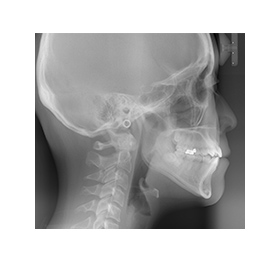

レントゲン写真を元に、

歯並びと

顎骨の分析をします

矯正カウンセリングにこられた方へ、WEBCEF(ウェブセフ)よる歯列矯正の解析レポートを作成し、詳しいご説明の上でご提供します。

この解析レポートでは、

・歯並びの左右の傾き

・お顔の中心に対して上顎歯列と下顎歯列がずれていないか

・ずれている場合には、どのように改善できるか

などを分析します。

レントゲン写真を元にして

実際に解析された画像

こちらの分析では上顎前歯と下顎前歯の両方が右側にずれていることがわかります。

このズレを矯正治療で正常な範囲まで移動させて治します。

標準(青線)の顎骨と、患者さま(赤線)の顎骨にどのような特徴があるのかを調べます。

標準と比較し分析したデータを

数値化します。

緑の項目が標準範囲内で正常、赤の項目は正常値から外れた診断結果として表示されます。

赤字の部分を標準範囲の緑へ変えていくことが、矯正治療の基本的な方針となります。

(※必ずしも、全てをグリーンにするわけではありません)